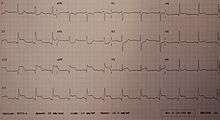

Most MIs occur due to coronary artery disease.[5] Risk factors include high blood pressure, smoking, diabetes, lack of exercise, obesity, high blood cholesterol, poor diet, and excessive alcohol intake, among others.[7][8] The mechanism of an MI often involves the complete blockage of a coronary artery caused by a rupture of an atherosclerotic plaque.[5] MIs are less commonly caused by coronary artery spasms, which may be due to cocaine, significant emotional stress, and extreme cold, among others.[9][10] A number of tests are useful to help with diagnosis, including electrocardiograms (ECGs), blood tests, and coronary angiography.[11] An ECG may confirm an ST elevation MI if ST elevation is present.[2] Commonly used blood tests include troponin and less often creatine kinase MB.[11]

A cardiac troponin rise accompanied by either typical symptoms, pathological Q waves, ST elevation or depression, or coronary intervention is diagnostic of MI.[69]

WHO criteria[70] formulated in 1979 have classically been used to diagnose MI; a patient is diagnosed with MI if two (probable) or three (definite) of the following criteria are satisfied:

- Clinical history of ischemic-type chest pain lasting for more than 20 minutes

- Changes in serial ECG tracings

- Rise and fall of serum cardiac biomarkers

Classification

Myocardial infarctions are generally classified into ST elevation MI (STEMI) and non-ST elevation MI (NSTEMI).[54] A STEMI is the combination of symptoms related to poor oxygenation of the heart with elevation of the ST segments on the electrocardiogram followed by an increase in proteins in the blood related to heart muscle's death.[16] They make up about 25 to 40 percent of cases.[16]

Electrocardiogram

For a person to qualify as having a STEMI, in addition to reported angina, the ECG must show new ST elevation in two or more adjacent ECG leads.[16] This must be greater than 2 mm (0.2 mV) for males and greater than 1.5 mm (0.15 mV) in females if in leads V2 and V3 or greater than 1 mm (0.1 mV) if it is in other ECG leads.[16] Previously, a recent left bundle branch block was considered the same as ST elevation, however, this is no longer the case.[16] In early STEMIs there may just be peaked T waves with ST elevation developing later.[16]